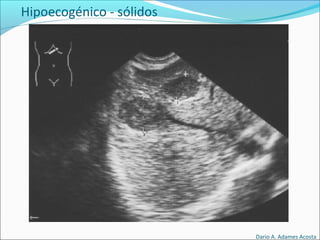

Sólidas

Hipoecogénicos

Hipoecogénico - sólidos

Dario A. Adames Acosta

• #60 Suele ser de este tipo las LOES correspondientes a tumores muy celulares, con poca fibrosis y sin estructuras glandulares muy desarrolladas y con vasos de paredes finas.

• #61 Harmatomas, tumores benignos